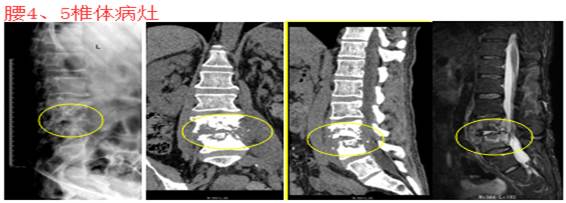

为保障患者安全,医院骨科建议患者转上级医院安置滤网后再行脊柱结核手术,患者考虑再三,拒绝转院,坚决要求在州人民医院进行手术。经多次复查下肢血管超声检查,左下肢深静脉血栓均未完全再通。患者亦因为左膝、腰背部疼痛影响睡眠、饮食等,多次提及并要求尽早手术,考虑到手术安全性,经全科及四川省人民医院俞阳副主任医师讨论后,向患方交代血栓脱落致死亡可能的前提下,签署术前相关医疗文书。